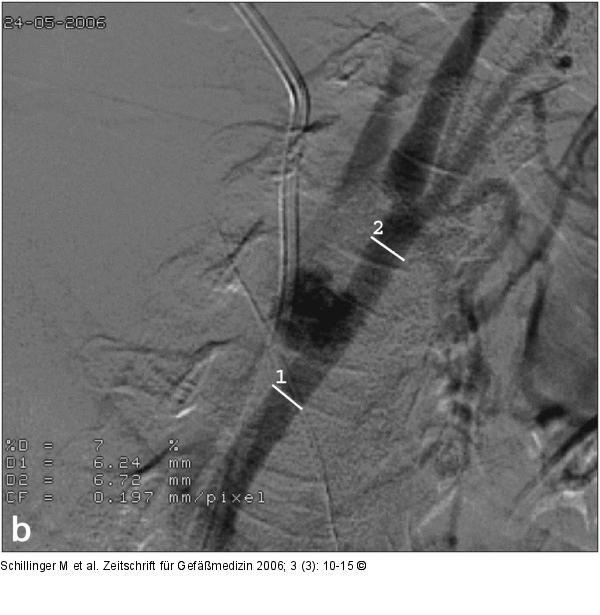

Abbildung 2b

Diagnostische Angiographie der rechten Arteria carotis communis mit einem 4 French-Sidewinder-II-Katheter: a) Darstellung eines etwa 20 mm im Durchmesser haltenden Aneurysma spurium der Arteria carotis communis 2 cm proximal der Karotisbifurkation. Weiters dargestellt sind der Schatten des zentralvenösen Katheters (Pfeil) sowie eine flaue Kontrastierung der Vena jugularis interna (Pfeilspitze) über eine AV-Fistel. b) Vergrößerung und Vermessung des Gefäßdurchmessers zur Auswahl eines passenden Stentgrafts nach Applikation von 0,1 ml Perlinganit: Die Arteria carotis communis mißt etwa 6,5 mm. |